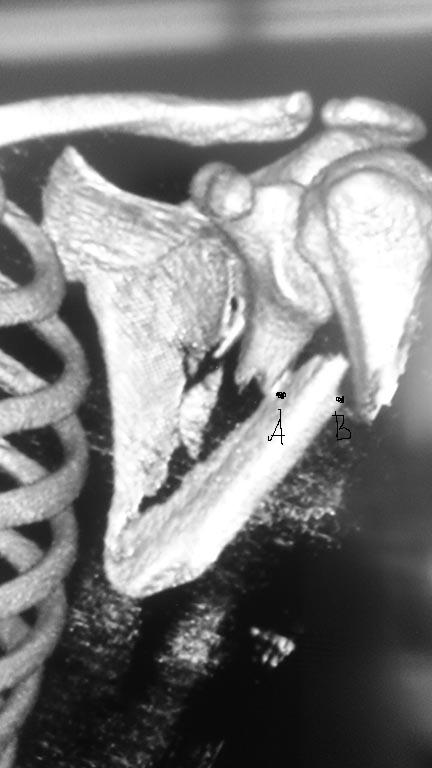

На рентгенограммах в прямой проекции или на 3D в прямой проекции проксимальный фрагмент лопатки (вместе с гленоидом) выглядит смещенным к средней линии т.е. медиализированным. На самом деле это ложная медиализация, смещается нижний фрагмент лопатки латерально. Смещение его более чем на 10мм (расстояние от т.А - латеральный край проксимального отломка до точки В - лат. край дистального отломка)является показанием к операции.

По прямой проекции 3D есть медиализация гленоида (не истинная, это является показанием к оперативному лечению. Доступ задний Judet или его модификация (подробности есть на АО сайте)одной реконструктивной пластины 3,5мм, уложенной по латеральному краю и задней нижней поверхности суставного отростка будет достаточно, если только все повреждения представлены в этой проекции.